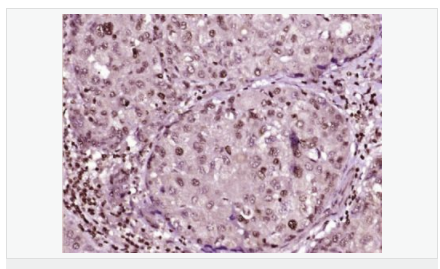

交叉反應(yīng):Human,Mouse,Rat(predicted:Dog,Pig,Rabbit,GuineaPig) 推薦應(yīng)用:IHC-P,IHC-F,ICC,IF,Flow-Cyt,ELISA

| 產(chǎn)品應(yīng)用 | ELISA=1:5000-10000 IHC-P=1:100-500 IHC-F=1:100-500 Flow-Cyt=1μg/Test ICC=1:100 IF=1:100-500 (石蠟切片需做抗原修復(fù)) not yet tested in other applications. optimal dilutions/concentrations should be determined by the end user. |